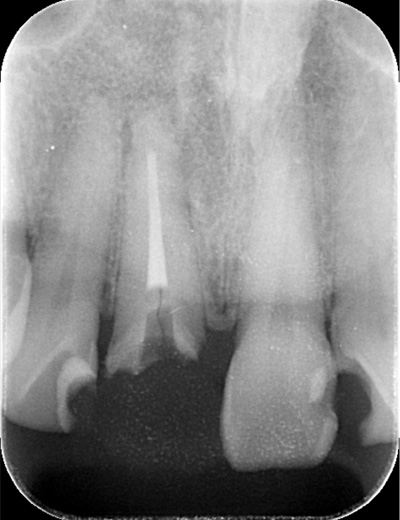

BEFORE

| 年代・性別 | 30代 男性 |

|---|---|

| 主訴 | 前歯が腫れた |

| 治療期間 | 約18ヶ月 |

| 費用 | 700,000円 |

| 治療内容 | インプラント、部分矯正、骨造成、結合組織移植、セラミック修復 |

| 治療に伴うリスク | インプラント周囲炎 セラミックの破折、脱離 |